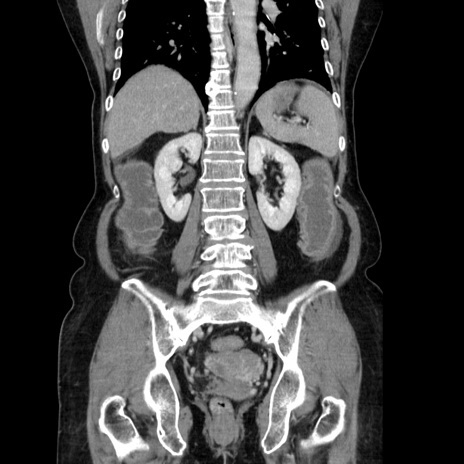

症例5(冠状断像)

【症例】70歳代女性

【主訴】お腹が張る

【現病歴】1週間くらい前から腹部膨満の自覚あり。昨日夜から増悪したため、本日救急外来受診。

【身体所見】意識清明、BT 36.5℃、BP 165/106mmHg、HR 80bpm、SpO2 98%、腹部:膨満、軟、自発痛・圧痛なし、触診にて不快感あり、腸蠕動音:減弱

【データ】WBC 12600、CRP 1.04